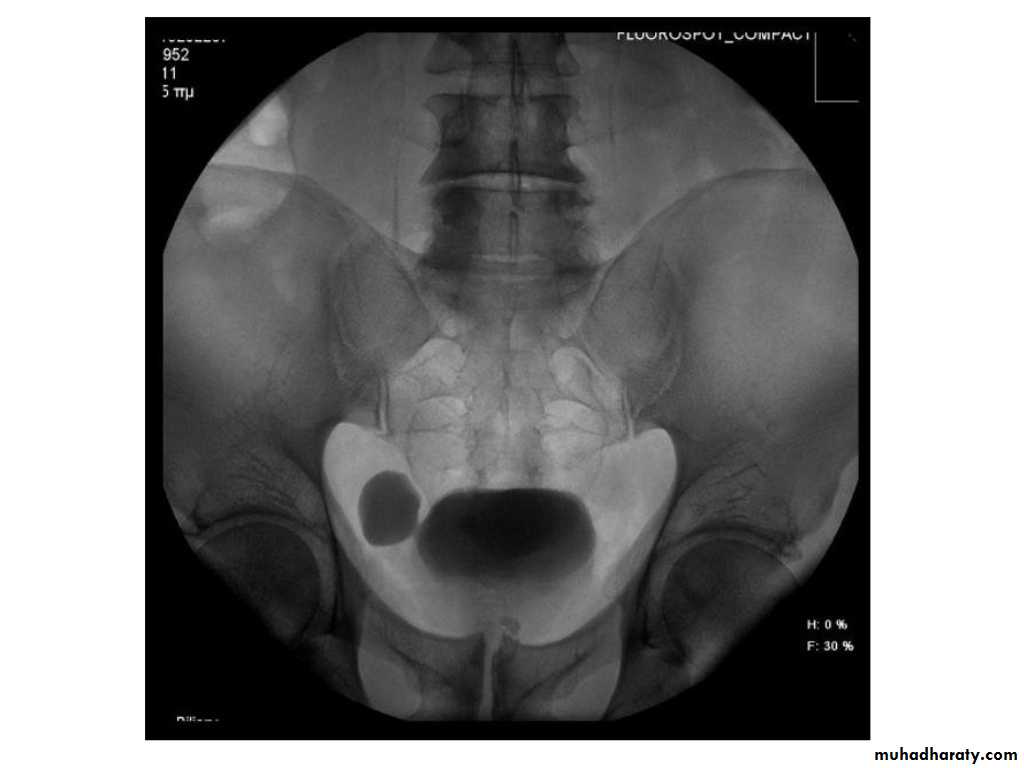

IVU shows

1. The kidneys at low position .2.Close to the spine with long axis parallel to the spine

3. Malrotation manifested by medially directed calyces.

4- The renal pelvis and ureters are anterior and lateral in position.

5- Hydronephrosis and calculi highly associated.